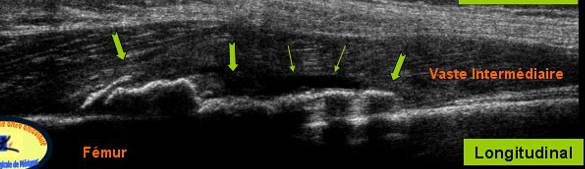

Echivalentul stadiului II al lui Rodineau se caracterizeaza prin

Fie o ingrosare focalizata, hiper ecogena,

centrala, sau a aponevrozie peri musculare

Fie de o dezorganizare mio-arhitecturala, care este inlocuita de

o zona cel mai frecvent hiper-ecogena

heterogena. Cautarea leziunilor mici este favorizata de miscari de contractie musculara

o zona cel mai frecvent

hiper-ecogena heterogena. Cautarea leziunilor mici este favorizata de miscari de contractie musculara